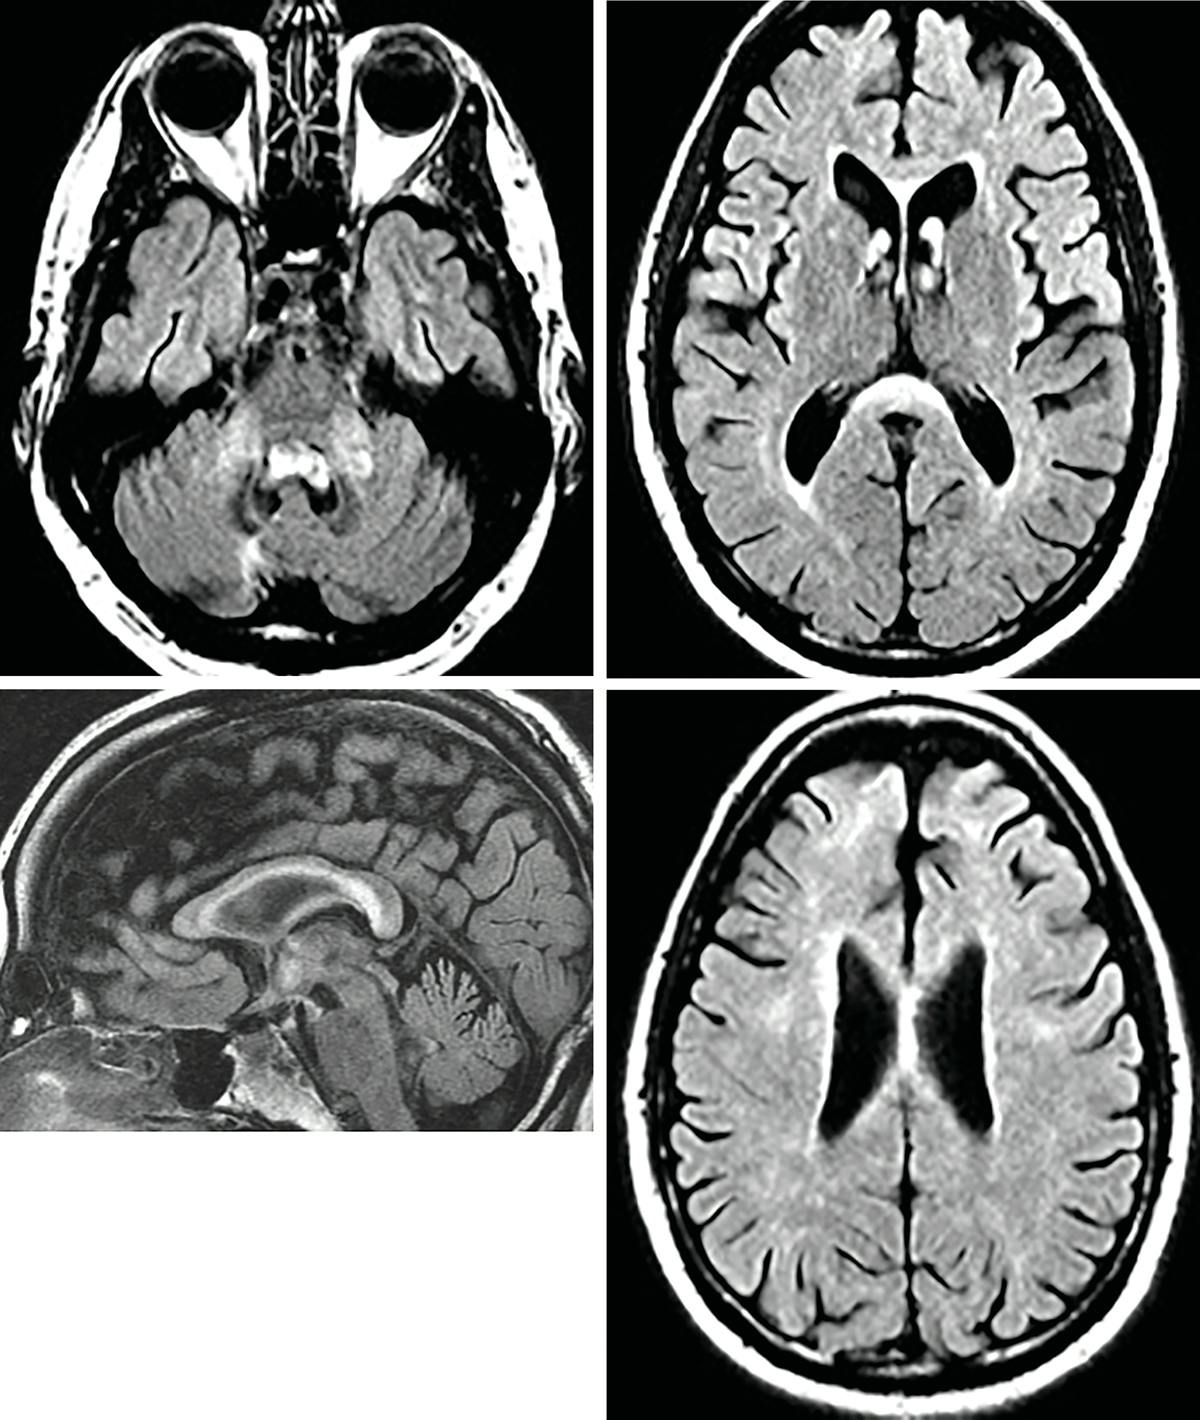

Symmetrical bilateral lesions in middle cerebellar peduncles suggest fragile X ataxia syndrome.

Established diagnostic criteria for FXTAS are summarized in the Table.4 The first and most important criteria is confirmed premutation of the FMRl gene (55-200 CGG repeats). If that is confirmed and there is 1 major neuroradiologic finding and 1 major clinical feature, definite FXTAS is diagnosed. Signal abnormalities with fluid-attenuated inversion recovery sequence (FLAIR) or T2 hyperintensities in the middle cerebellar peduncles (MCPs) on brain MRI should raise suspicion for FXTAS because this is a major radiologic sign. White matter lesions in the splenium of the corpus callosum are often seen as well, which is considered a minor radiologic sign.

In the case of Mr J, presented here, the MCP lesion was likely unilateral on initial imaging and then bilateral on subsequent follow-up imaging. Both MCP and corpus callosum lesions can be seen in both MS and FXTAS.6 The confluent nature of the lesions, in Mr J’s case, along with the symmetry of MCP abnormalities are not typical of MS.